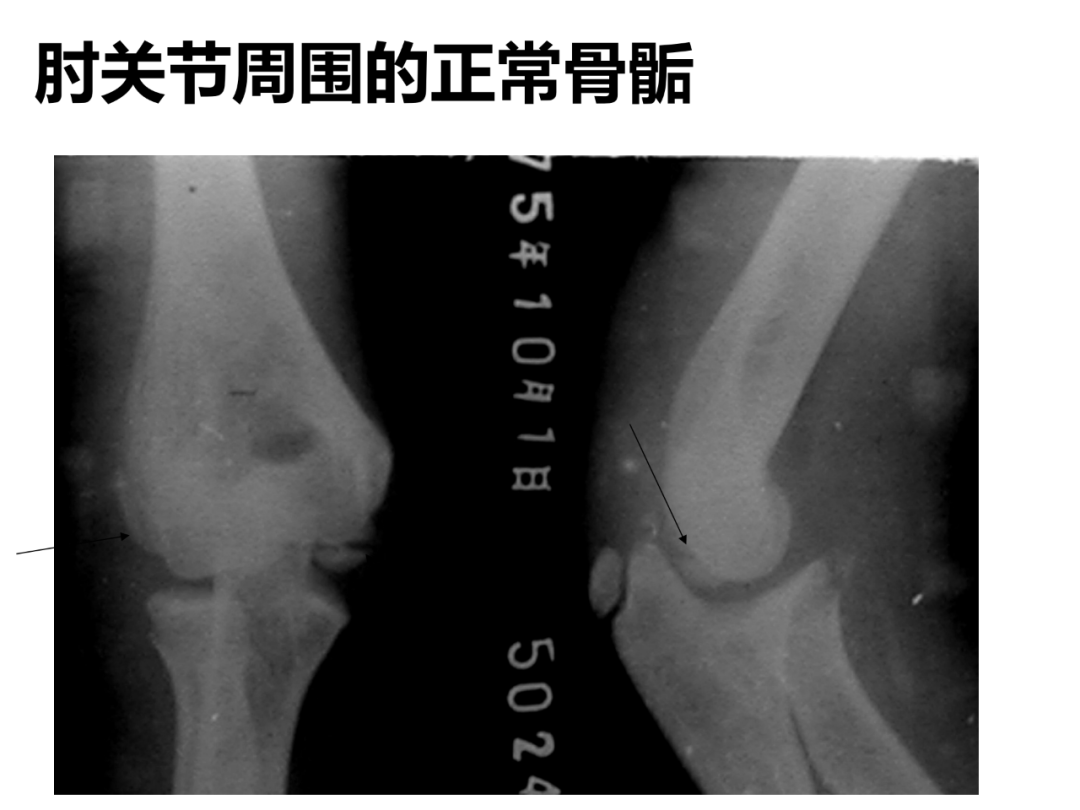

小儿骨科X线片汇总,临床读片宝典!